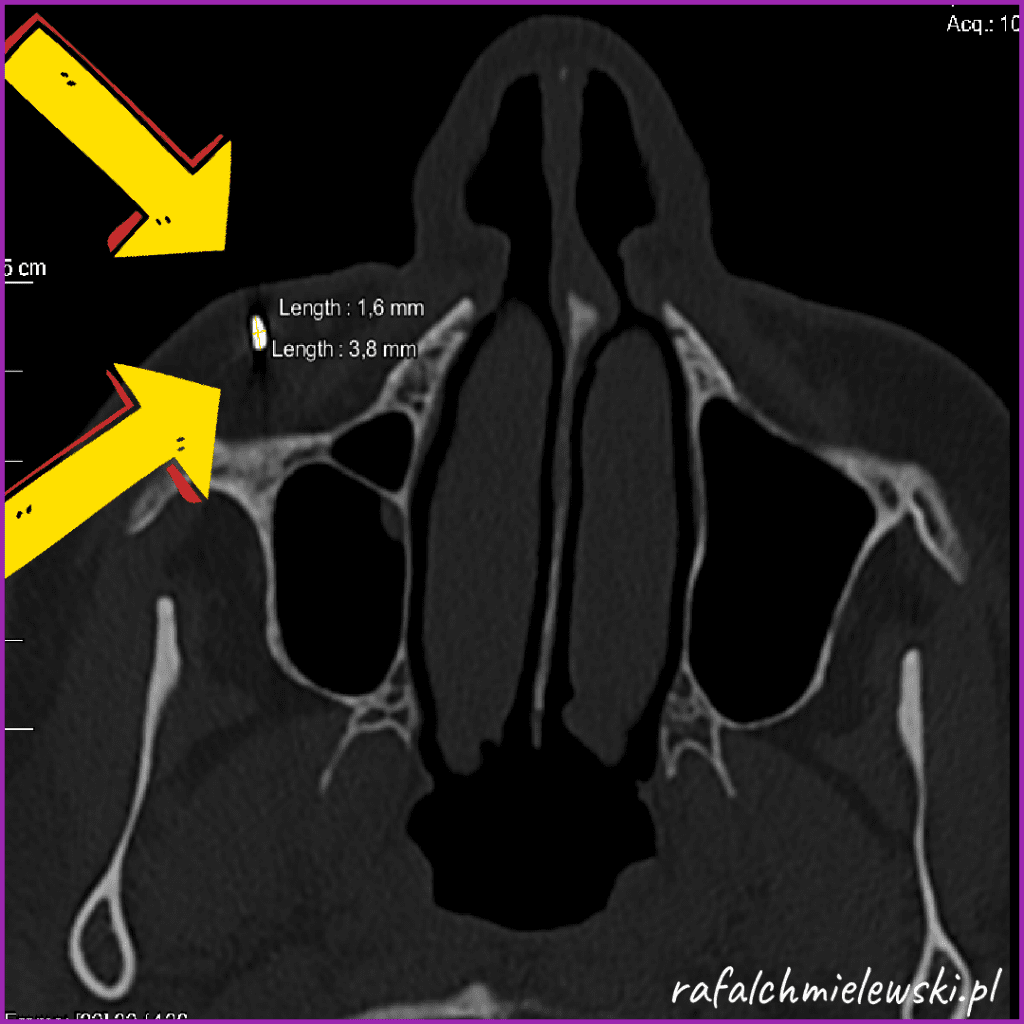

TK zatok - mataliczne ciało obce policzka

Metaliczne ciało obce, kształtu owalnego, zlokalizowane w tkankach miękkich policzka prawego. Wymiary w płaszczyźnie osiowej 3,8 x 1,6 mm. Fragment gwoździa odłupany podczas uderzenia młotkiem ponad 20 lat temu